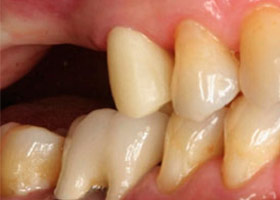

完成照片